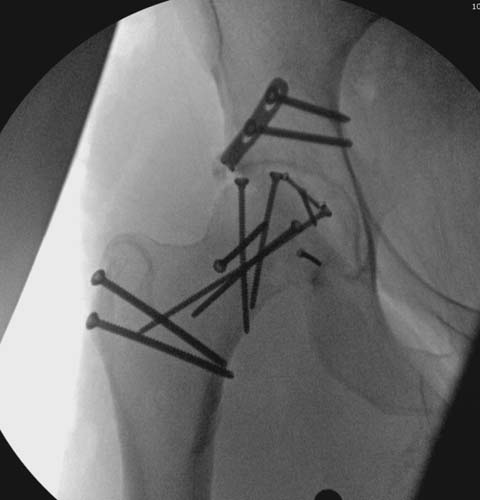

Здесь клинические примеры: Первый случай передний доступ, второй с ICP

monitor Flipp Trochanteris

и с переломом заднего края.